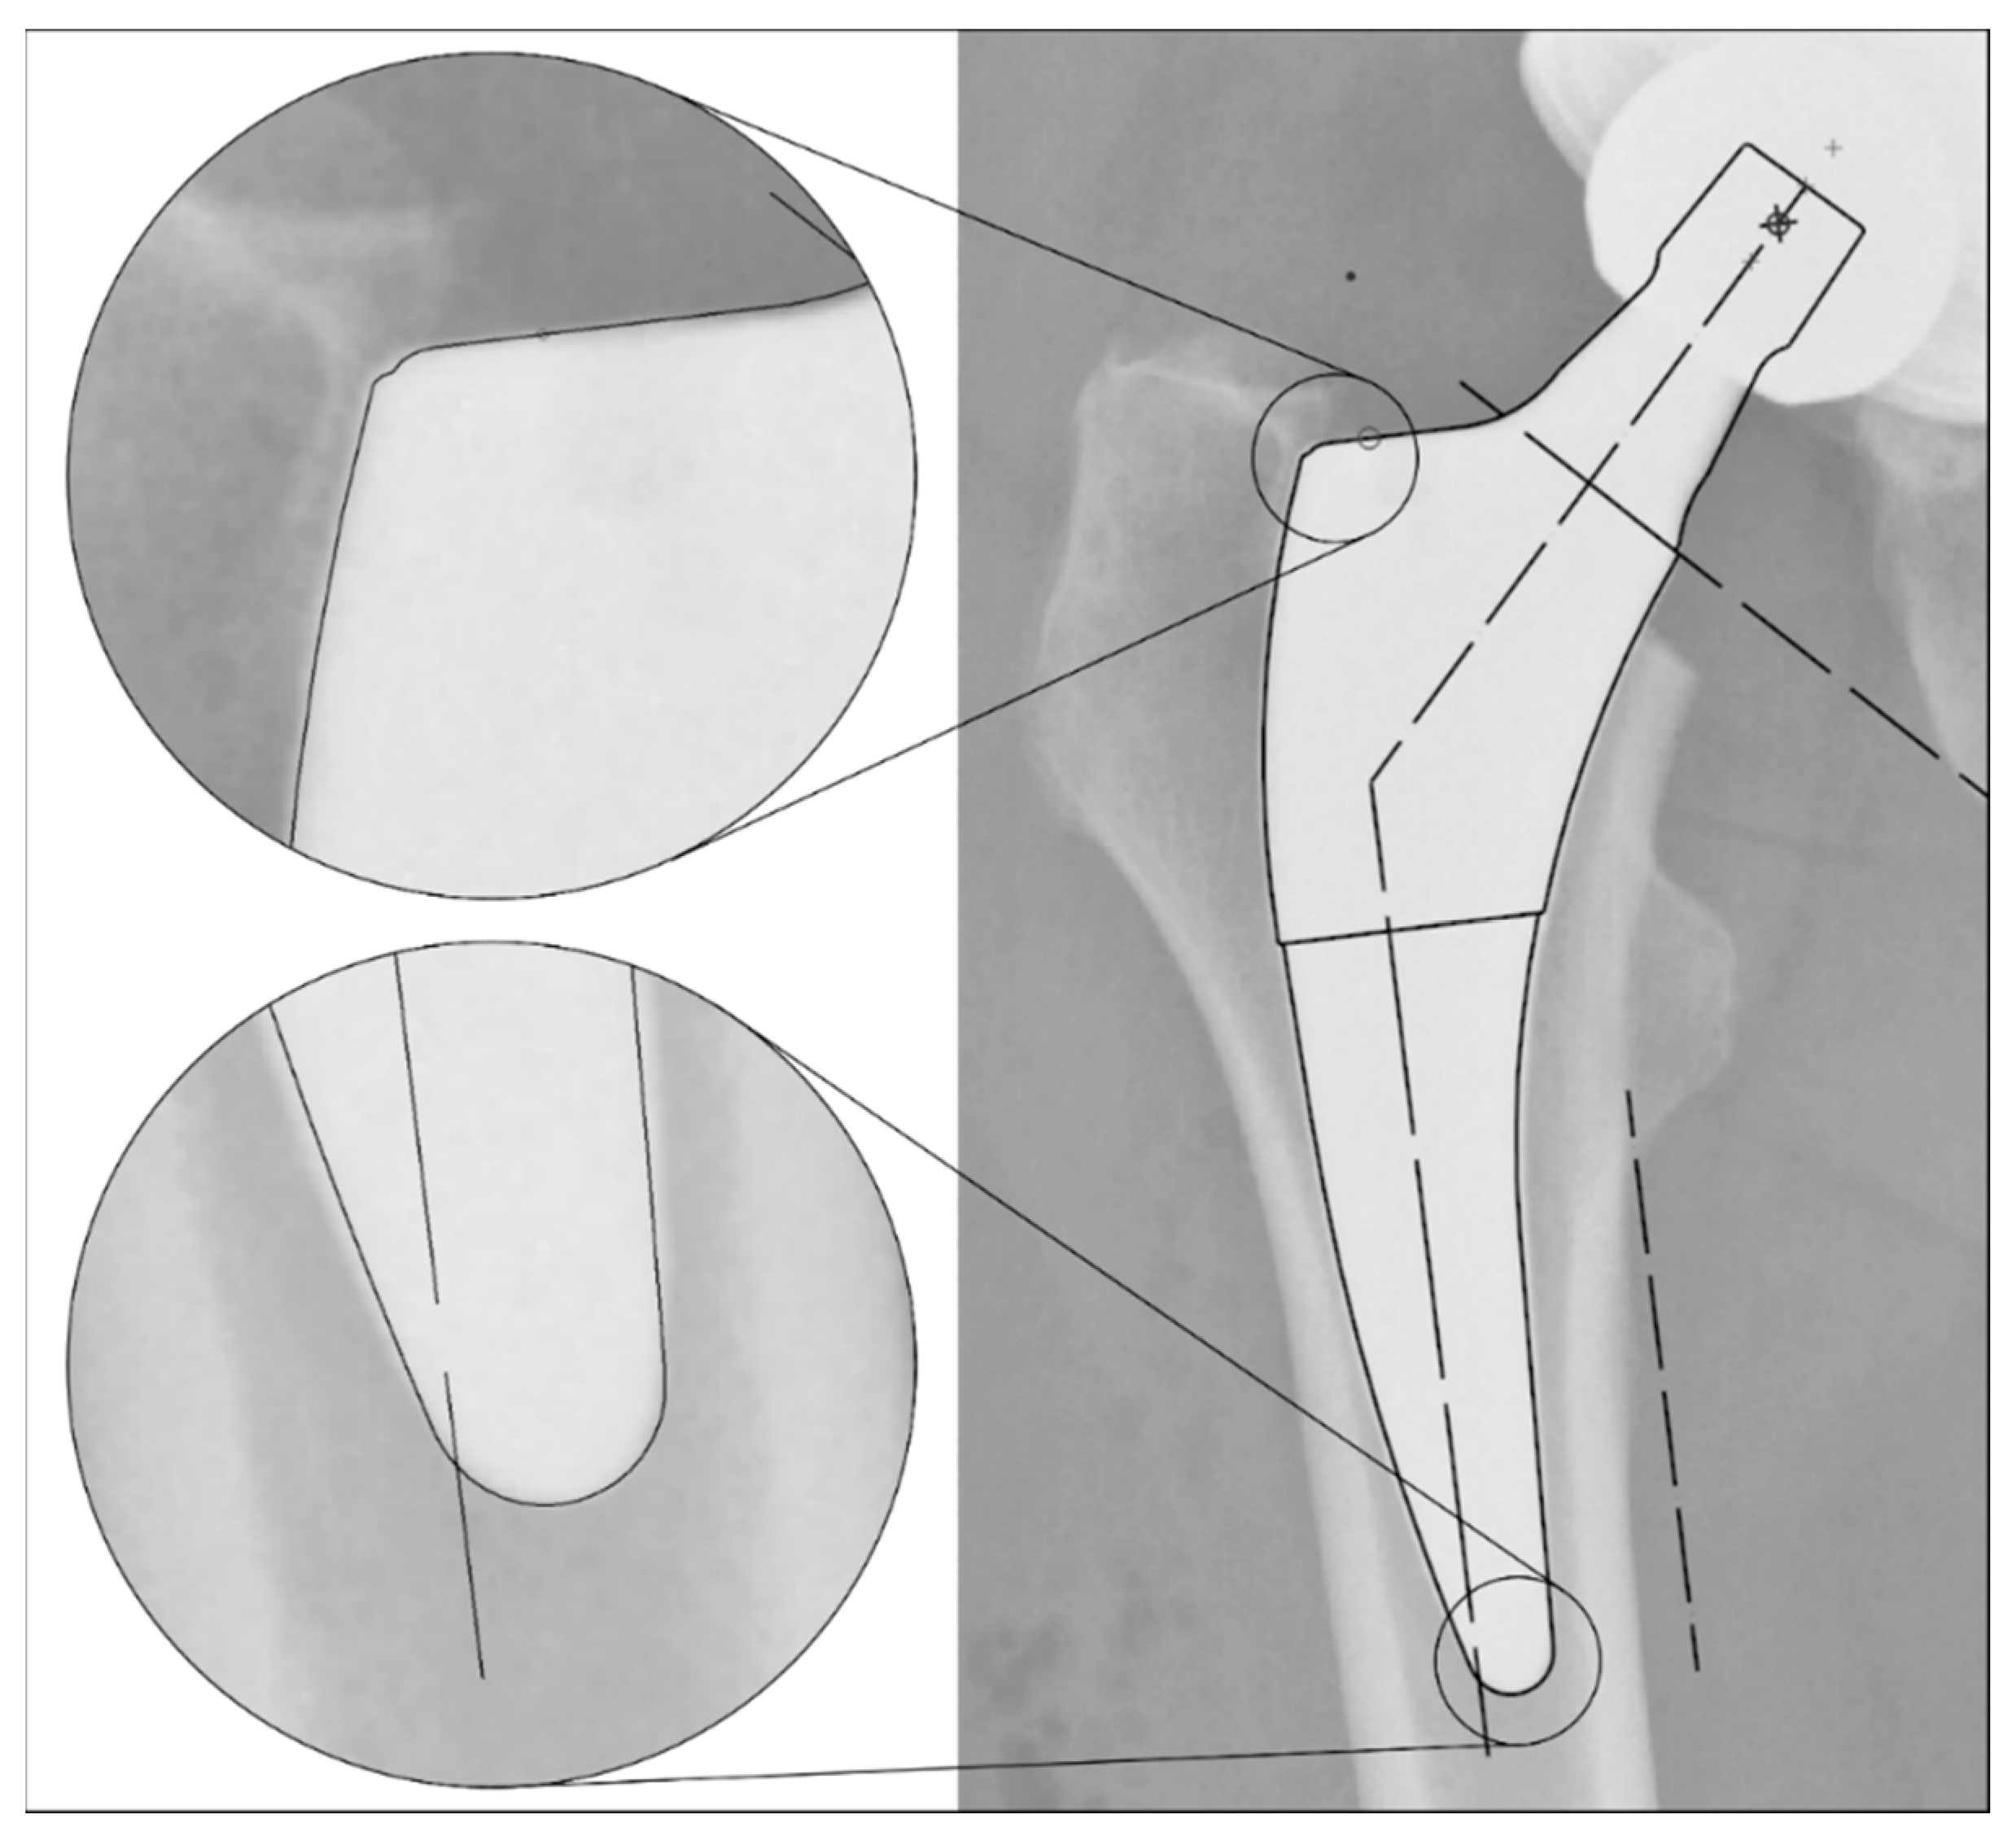

The radiographs were analysed with TraumaCad® software (Brainlab AG, Munich, Germany). We used only standardised deep-centered anteroposterior X-rays of the pelvis, with the central beam perpendicular to the midline and centered over the symphysis, and the legs positioned in 15° of internal rotation with the patient in the supine position. The images were calibrated by measuring the length of the depicted stem from its shoulder to its tip and equating it with the corresponding planning template. In this way, we could avoid any possible errors in our established calibration method with a reference sphere, which can be placed too far away from the central beam or too far away from the film. The measurements of the stem position were subsequently taken on the same axis to neutralise distortions caused by varying flexion and rotation positions of the leg during radiography (Figure 2). The varus/valgus alignment of the stems was determined by measuring the angle between the longitudinal axis of the stem and the longitudinal axis of the femoral canal (Figure 3). Subsidence was determined by measuring the distance from the shoulder of the stem to a clearly definable point at the greater trochanter in the previously determined longitudinal axis of the stem (Figure 4). Due to possible osseous changes over time, such as enthesiopathies or ossifications at the tip of the greater trochanter, defining this point was crucial to measure the correct distance.

Figure 4. Method for measuring the stem position: (1) Identification of a clearly definable point on the greater trochanter, which appears identically on all radiographs up to 10 years postoperatively. (2) Calibration of the image using a planning template, as shown in Figure 2. (3) Determination of the femoral longitudinal axis. (4) Distance measurement of the defined point to the prosthetic shoulder along the femoral longitudinal axis.